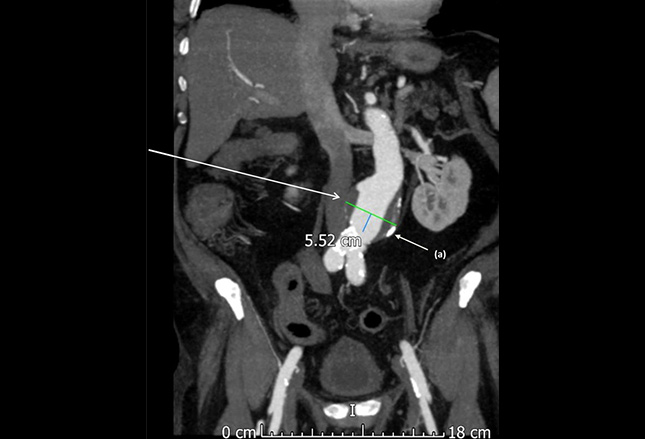

CT扫描对比揭示了无症状的老年男性中的腹主动脉瘤。动脉瘤壁上和远端主动脉(a)有钙化的动脉粥样硬化斑块。